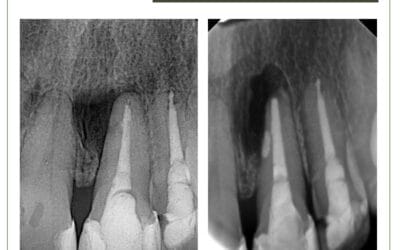

Reabsorção radicular cervical externa

Reabsorção radicular cervical externa. Paciente 30 anos, sexo feminino, com diagnóstico de reabsorção radicular...